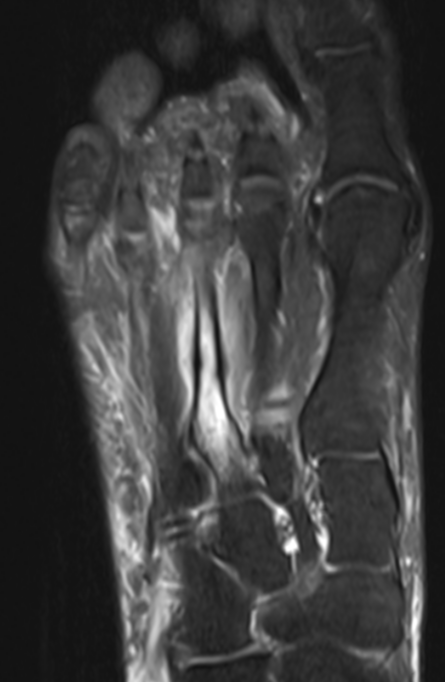

3. Metatarsal stress fracture